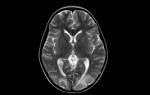

Для более детального изучения состояния здоровья применяются различные методы инструментальной диагностики, такие как:

- Ангиография. Этот метод позволяет оценить состояние сосудов с использованием контрастного вещества, а также выявить наличие тромбов, атеросклероза, аневризм и онкологических заболеваний.

- Ангиосканирование. Используется на начальных этапах диагностики цереброваскулярных заболеваний. Это один из доступных и быстрых методов, который безопасен даже при многократном применении.

- Транскраниальная допплерография. Исследование проводится с помощью ультразвука, что позволяет определить скорость кровотока и выявить возможные нарушения.

- Сцинтиграфия мозга — это простой метод, практически не имеющий противопоказаний. Он заключается во введении радиоактивного препарата в вену, после чего через 15 минут выполняется сканирование. За это время радиоизотоп распределяется по организму и накапливается в тканях с патологическими изменениями.

Также важную роль в диагностике играют магнитно-резонансная и компьютерная томографии.